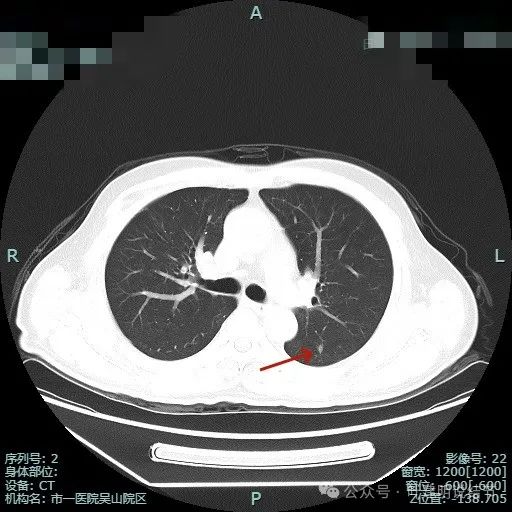

明明典型浸润性癌影像表现病理结果却是原位癌,原位癌也可表现为混合密度?

病史摘要:患者 3 个月前社区体检发现肺结节,就诊时医生考虑左上病灶基本为肺癌且倾向浸润性,因首次发现,建议口服抗炎 10 - 12 天,间隔 3 个月复查。此次复查无吸收好转及明显进展,拟手术治疗。诊疗过程:体格检查未提及。影像检查显示左上叶胸膜下混合密度结节,有血管弯征、胸膜牵拉等诸多恶性特征,下叶有次病灶。临床考虑左上叶病灶恶性且浸润性癌可能性大,建议手术。术中快速切片报腺癌